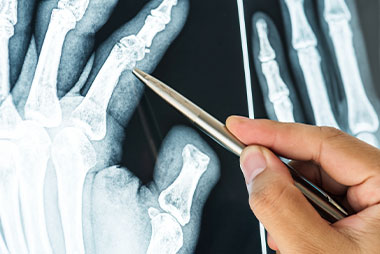

Trauma y Manejo de Fracturas

TALLER DE ESPECIALIZACIÓN Y PERFECCIONAMIENTO

Institución Badra te invita al taller de Trauma y Manejo de Fracturas, dictado por médicos especialistas en Emergentología. El presenta taller pretende abordar, desde el punto de vista de los primeros auxilios, las eventualidades que pueden comprometer la vida del paciente por diferentes fracturas. Los participantes aprenderán a obtener ayuda médica ante una fractura, a hacer uso de férula, las maniobras correspondientes, etc. Te esperamos!

- Introducción y generalidades sobre fracturas.

- Clasificación de las fracturas.

- Complicación de las fracturas.